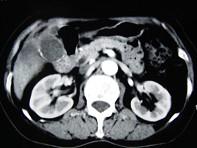

问题 女,66岁,右上腹痛,发热伴有黄疸两月余,消瘦、纳差,影像检查如图,最可能的诊断是()

选项 A.胆囊结石及脂肪肝 B.胆囊结石及肝血管瘤 C.胆囊癌肝转移 D.肝内胆管细胞癌 E.胆囊癌及原发性肝癌

答案 C